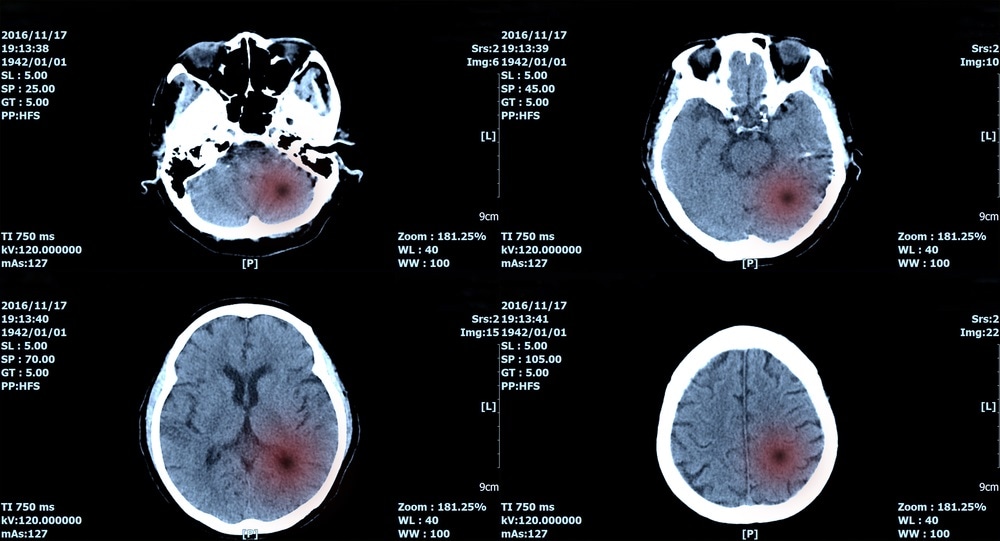

A brain tumor is a mass of abnormal cells that grow in the brain. In 2016 alone, there were 330,000 incident cases of brain cancer and 227,000 related-deaths worldwide. Early detection is crucial to improve patient prognosis, and thanks to a team of researchers, they developed a new imaging technique and artificial intelligence algorithm that can help doctors accurately identify brain tumors.

Image Credit: create jobs 51 / Shutterstock.comImage Credit: create jobs 51 / Shutterstock.com